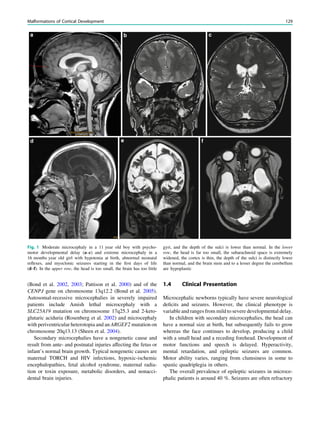

Fig. 1 Digital photogram of the brain surface before placement of a

subdural 8 9 8 grid. A second photogram was taken after grid

placement and digitally replaced by a schematic drawing detailing the

results of electrical stimulations and ictal/ intraictal EEG activity. Blue

grid contacts represent the eloquent zone, which is the motor cortex in

this case. The black area represents the epileptogenic lesion, defined

as the radiographic lesion that causes the seizures. The yellow area is

the seizure onset zone, defined as the area from which the clinical

seizures are generated. The seizure onset zone is often, but not

necessarily, congruent with the epileptogenic zone, defined as the

cortex area indispensable for the generation of seizures